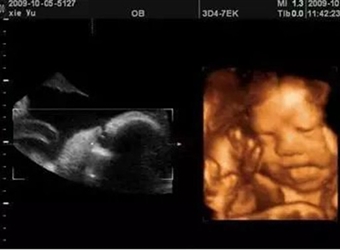

有些宝宝在做四维彩超的时候,不配合宝妈,所以宝妈们一次二次都过不了,弄得宝妈每次做四维彩超都是非常紧张的,那么妈妈做四维彩超不通过的原因有哪些呢?

在做四维彩超的时候,宝宝非常不配合,不翻身让宝妈们苦恼不已,那么四维胎儿趴着该怎么办呢?本文就给大家带来了四维宝宝翻身的技巧,感兴趣的家长赶紧来了解…

四维是判断胎儿畸形的一种主要手段,但四维彩超不是你想做就能做的。想做四维胎儿和孕妇必须满足一些发育条件,那么孕妇什么时候做四维最好呢?